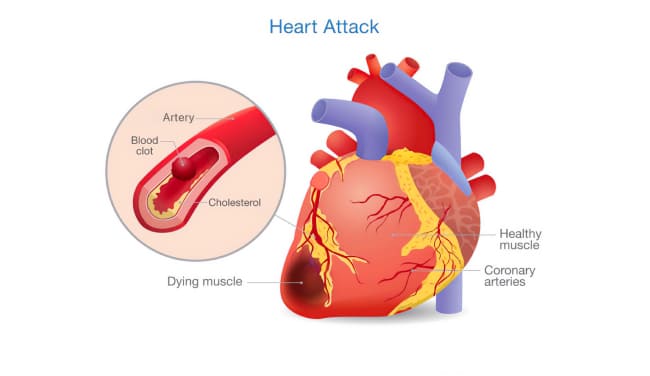

Semua orang tahu bahwa tekanan darah tinggi, stroke, dan serangan jantung adalah konsekuensi dari pembuluh darah yang "terkontaminasi" dengan kolesterol. Namun, sedikit yang tahu bahwa ini hanyalah puncak gunung es. Pembuluh darah yang "kotor" adalah penyebab dari 9 dari 10 penyakit kronis yang dianggap tidak dapat disembuhkan.

Dan, tentu saja, raja pembuluh darah yang buruk, Yang Mulia Hipertensi. Hipertensi adalah ayah dari stroke dan saudara serangan jantung.

Semua orang tahu bahwa kolesterol itu buruk. Dialah yang menyumbat pembuluh darah kita, menyempitkannya, dan mengganggu sirkulasi darah. Tapi itu bukan satu-satunya penyebab, bukan?

Ya, Anda benar. Plak kolesterol atau "plak aterosklerotik" menyumbang sekitar 65-70% dari kontaminasi vaskular.

Pada usia 50 tahun, hingga 5 kg plak kolesterol terakumulasi dalam pembuluh darah seseorang. Endapan kolesterol menyempitkan lumen pembuluh darah 4-5 kali.

Bayangkan. Jika lumen normal wadah adalah jari Anda, maka 5 kg plak kolesterol mengurangi lumen menjadi ukuran 4 korek api.

Plak kolesterol sendiri tidak mengancam jiwa. Ya, kualitas hidup menurun, tekanan meningkat, ada sakit kepala dan nyeri sendi, kelemahan, dan apatis. Yang jauh lebih berbahaya adalah massa trombotik dan kristal kalsium, yang juga terakumulasi dalam pembuluh darah kita.

Jika trombus cukup besar, ia dapat sepenuhnya menyumbat pembuluh darah, memutus suplai darah ke organ yang dilayaninya. Kondisi ini dikenal sebagai iskemia.

Stroke iskemik terjadi akibat penyumbatan pembuluh darah di otak. Infark miokard, atau serangan jantung, terjadi ketika ada penyumbatan di arteri koroner jantung. Organ lain juga bisa terkena iskemia. Misalnya, penyumbatan di hati dapat menyebabkan iskemia hati, sementara penyumbatan di paru-paru dan ginjal dapat menyebabkan kegagalan organ ini. Wasir, pada kenyataannya, adalah bentuk iskemia vaskular yang mempengaruhi daerah rektal. Terakhir, jika pembuluh darah di kaki tersumbat, itu bisa menyebabkan kematian jaringan seiring waktu, kondisi yang dikenal sebagai gangren.